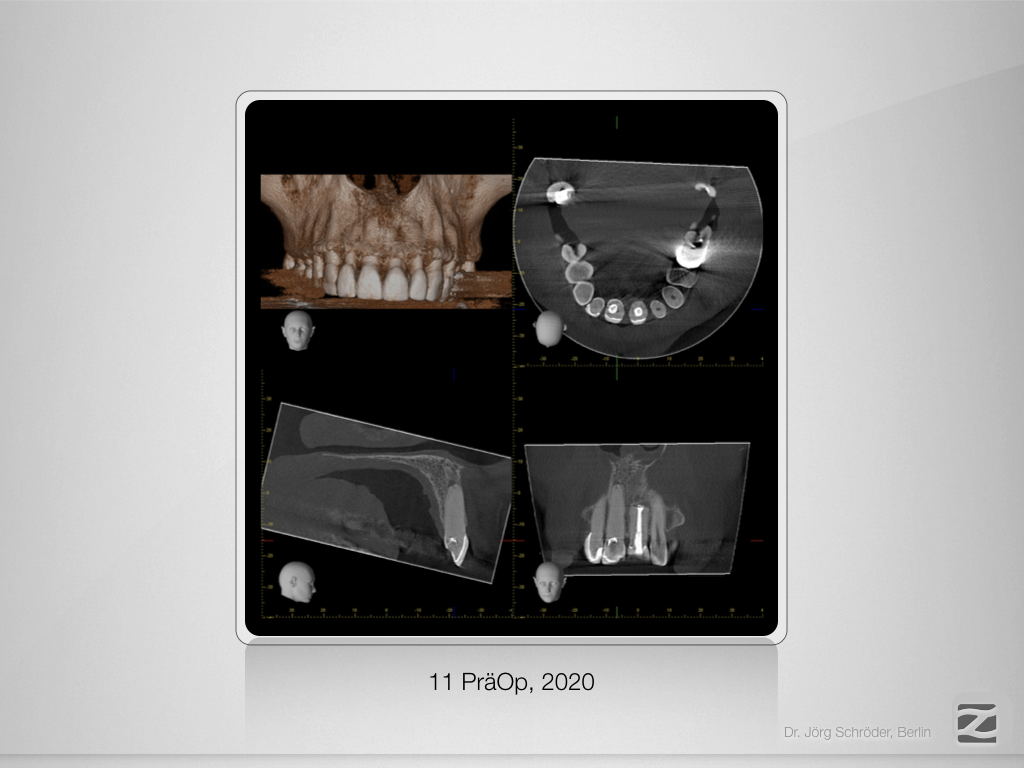

„Guided“ geplant und „Guarded“ gemacht